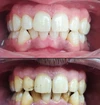

اعوجاج الأسنان